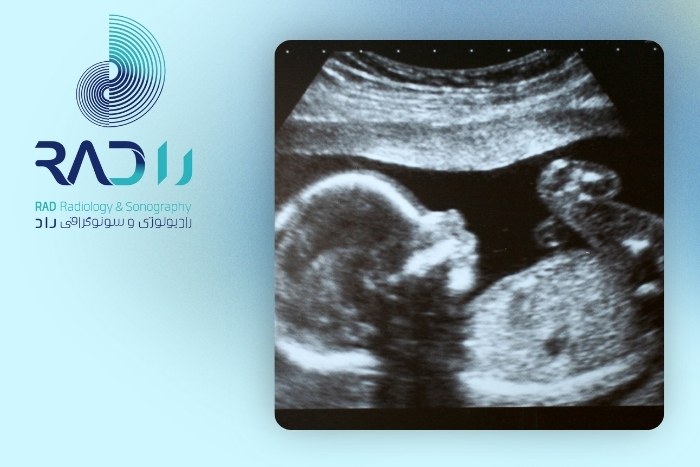

سونوگرافی آنومالی یا بررسی ناهنجاریها (هفته ۱۸ تا ۲۲)

بررسی ساختار مغز، قلب، کلیه، ستون فقرات و سایر اعضای بدن جنینمشخص شدن جنسیت در صورت تمایل والدین

بررسی موقعیت جفت و میزان مایع آمنیوتیک

یکی از مهمترین سونوگرافیهای دوران بارداری است و نباید از آن صرفنظر کرد.